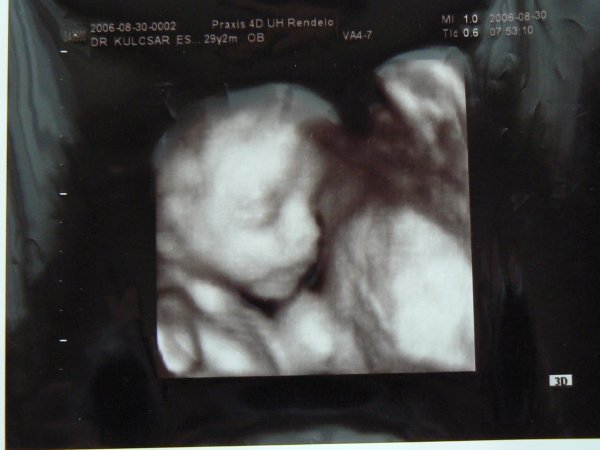

Várom a tegnapi uh eredményét

Meg képet meg mindent